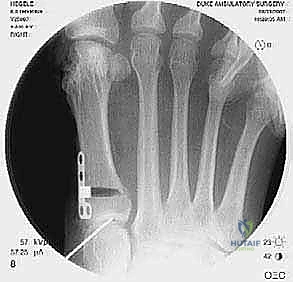

- يتم تحديد مواقع المسامير أو الشرائح المعدنية من الجراحة السابقة وإزالتها (Hardware Removal). قد تكون هذه الخطوة صعبة إذا نما العظم فوق المسامير.

إذا كان الفشل ناتجًا عن تصحيح غير كافٍ في الجراحة الأولى، وكان المفصل لا يزال سليمًا (لا توجد خشونة شديدة)، يقوم الدكتور هطيف بإجراء قطع عظمي جديد (مثل تقنية Scarf أو Chevron) لإعادة توجيه العظم وتثبيته بمسامير تيتانيوم حديثة لا تسبب تهيجًا.

إذا كان سبب التكرار هو "فرط الحركة" في مفصل منتصف القدم (TMTJ)، فإن الحل الوحيد لمنع التكرار المستقبلي هو دمج (إيثاق) هذا المفصل. يزيل الدكتور هطيف الغضروف من المفصل، يصحح زاوية العظم، ويثبته بشريحة معدنية قوية ومسامير حتى يلتحم العظمان معًا. هذه العملية تعالج أصل المشكلة من الجذور.

في هذه العملية، يتم إزالة الغضروف التالف من مفصل الإصبع الكبير، ودمج العظام معًا في وضع مستقيم قليلاً للأعلى للسماح بالمشي الطبيعي. يتم التثبيت باستخدام شريحة ومسامير متقاطعة. النتيجة هي إصبع مستقيم، خالٍ تمامًا من الألم، ولا يمكن أن يعود للتشوه أبدًا.